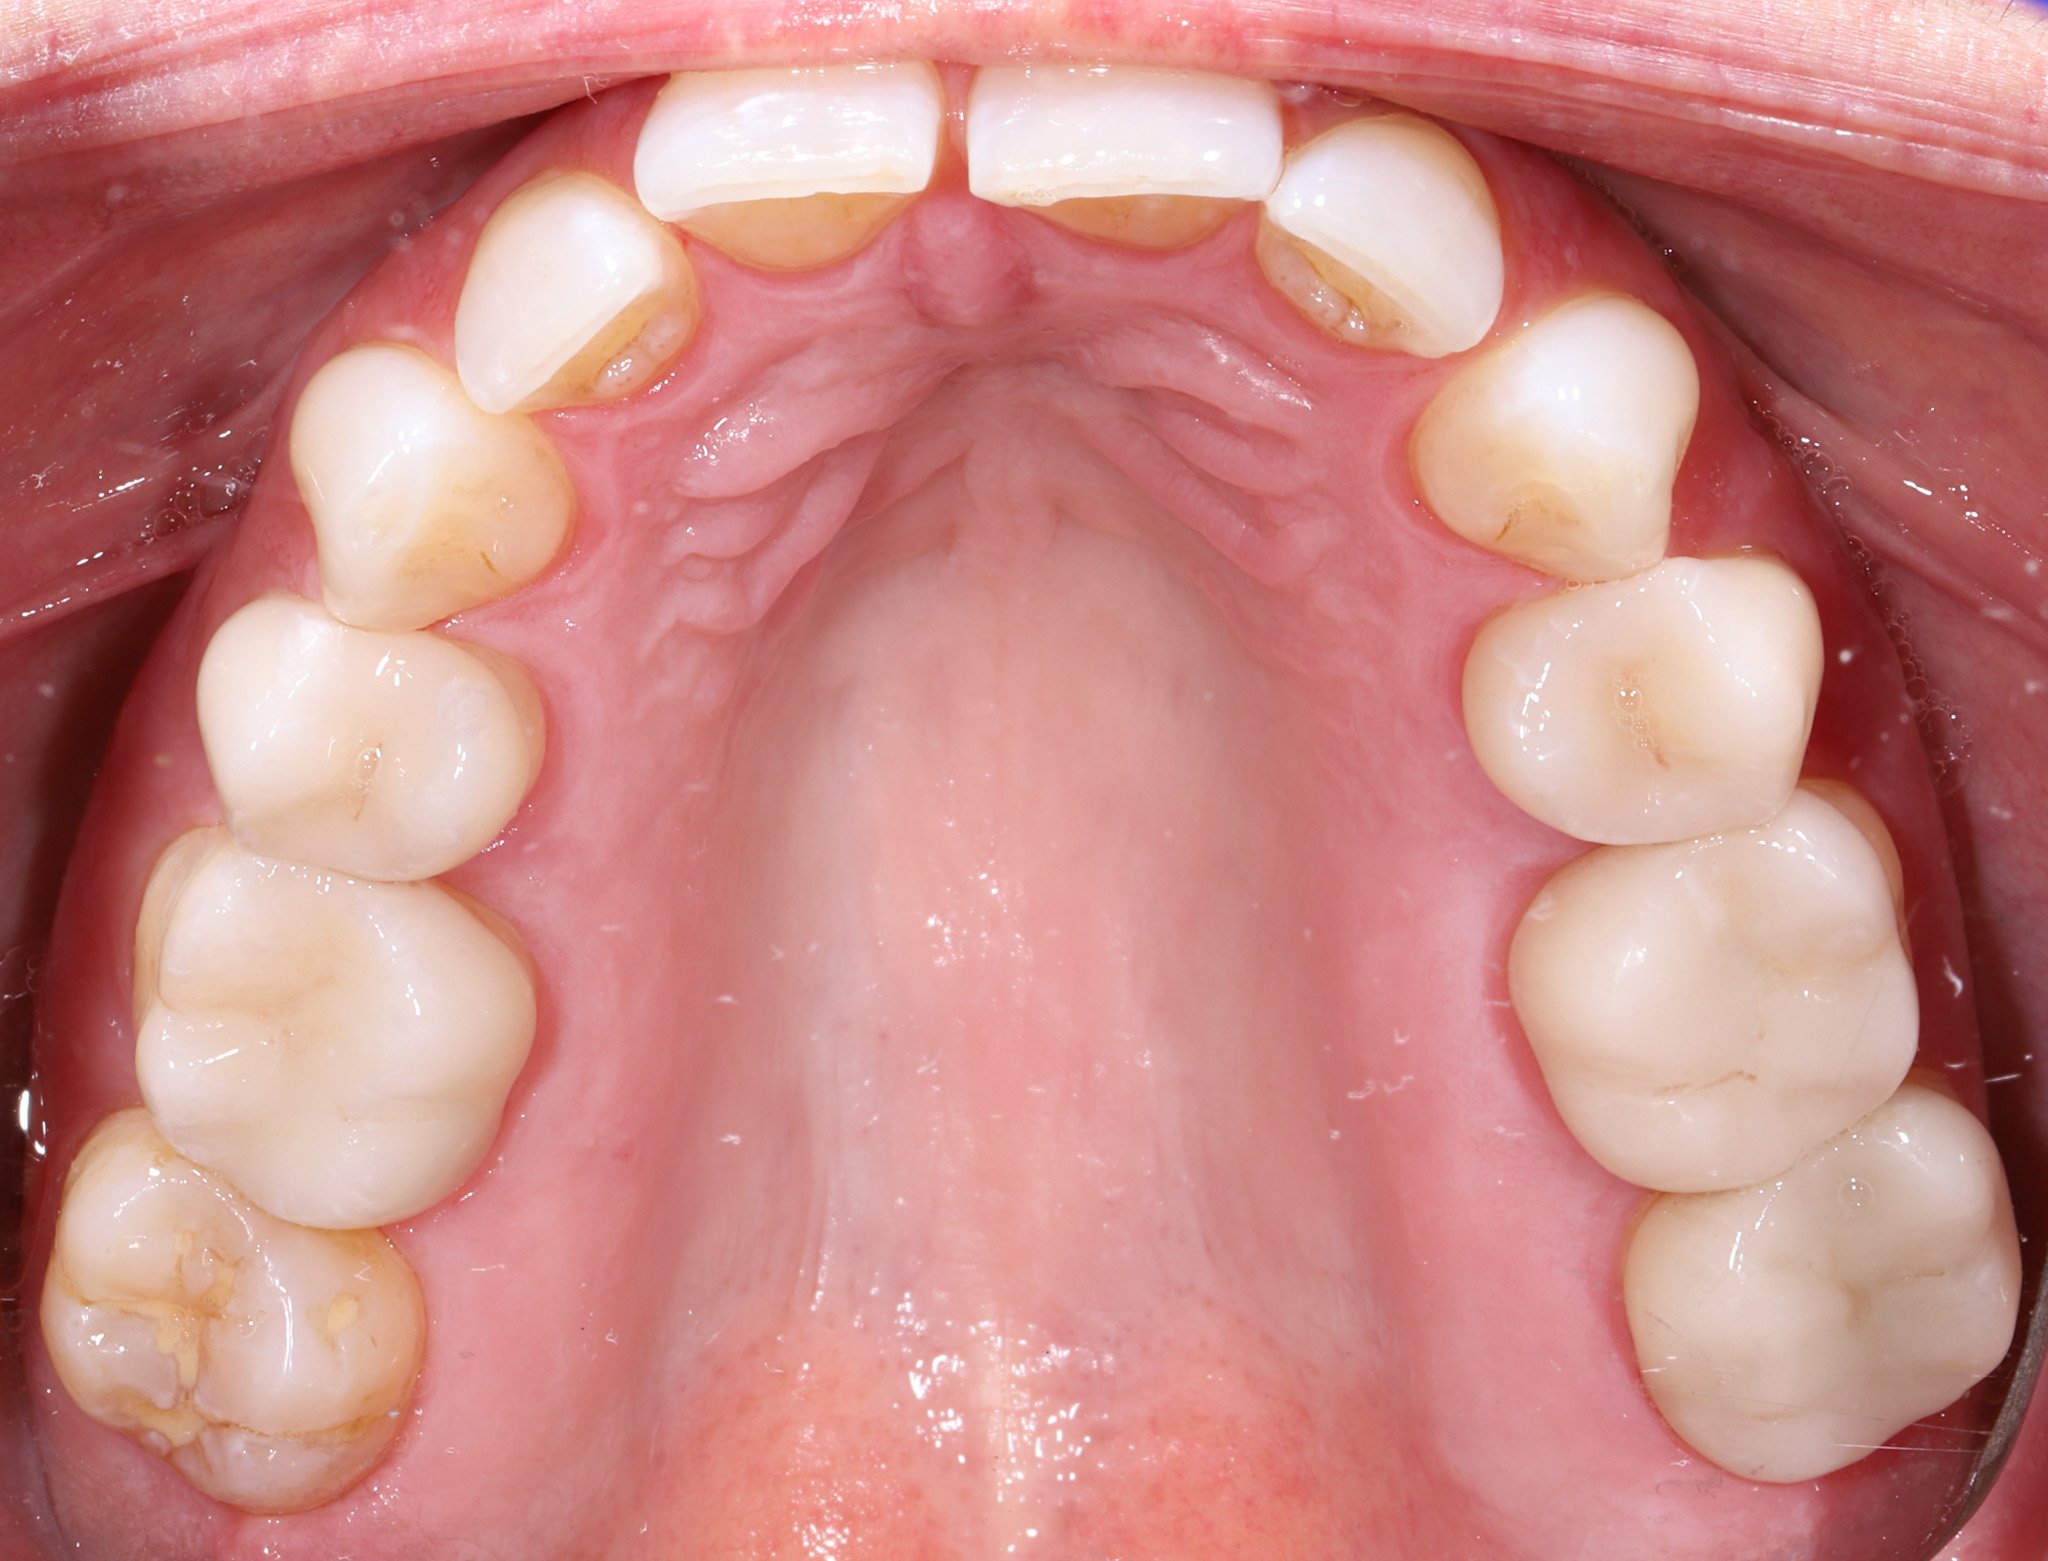

Inside of a person's mouth showing upper teeth, some with dental fillings, and healthy gums.

Before: Cracked teeth, leaking fillings, decay

Close-up of the upper teeth and roof of mouth, showing some dental decay on molars, in a person's mouth.

After: Sealed and protected teeth that blend with natural contours